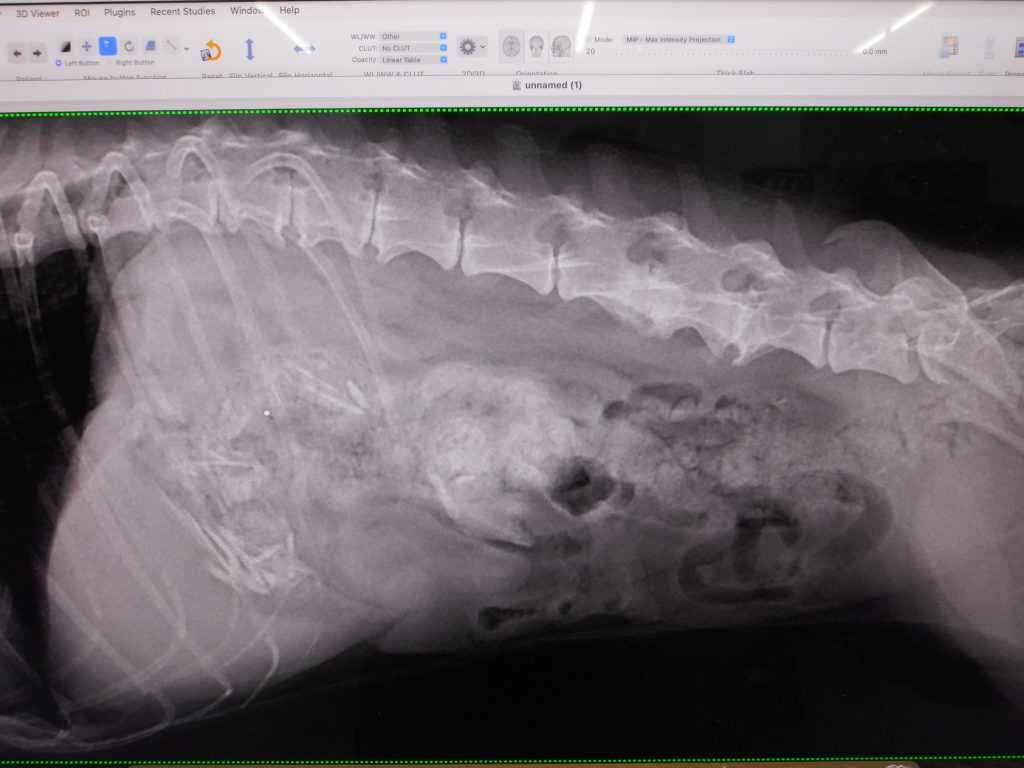

診断:フライドチキンの骨ごと盗食

どこにあるか?

ココです

骨ごといってます